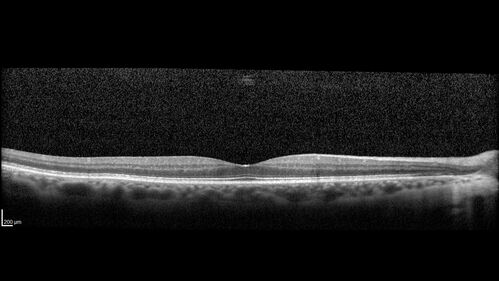

Branch retinal vein occlusion with macular edema

71 year old man Starting about 2 weeks ago the left eye was blurred. The right eye is seeing well.

VA OD: sc20/25+2 NccJ1+

VA OS: sc20/63+2 PH20/50-2 Ncc20/400

IOP: TP: OD:19 OS:16